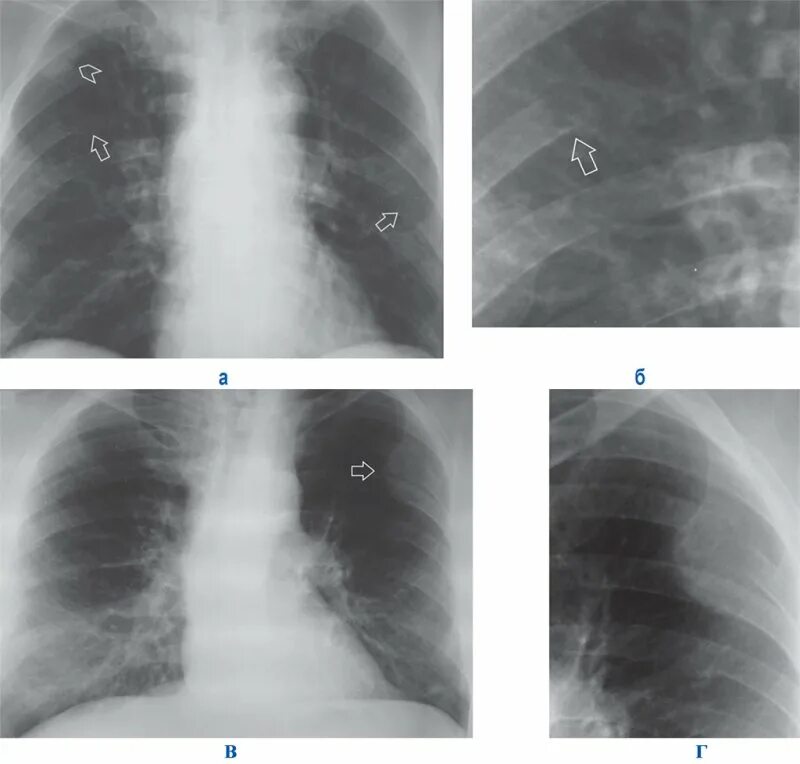

Метастазы в легких терапия